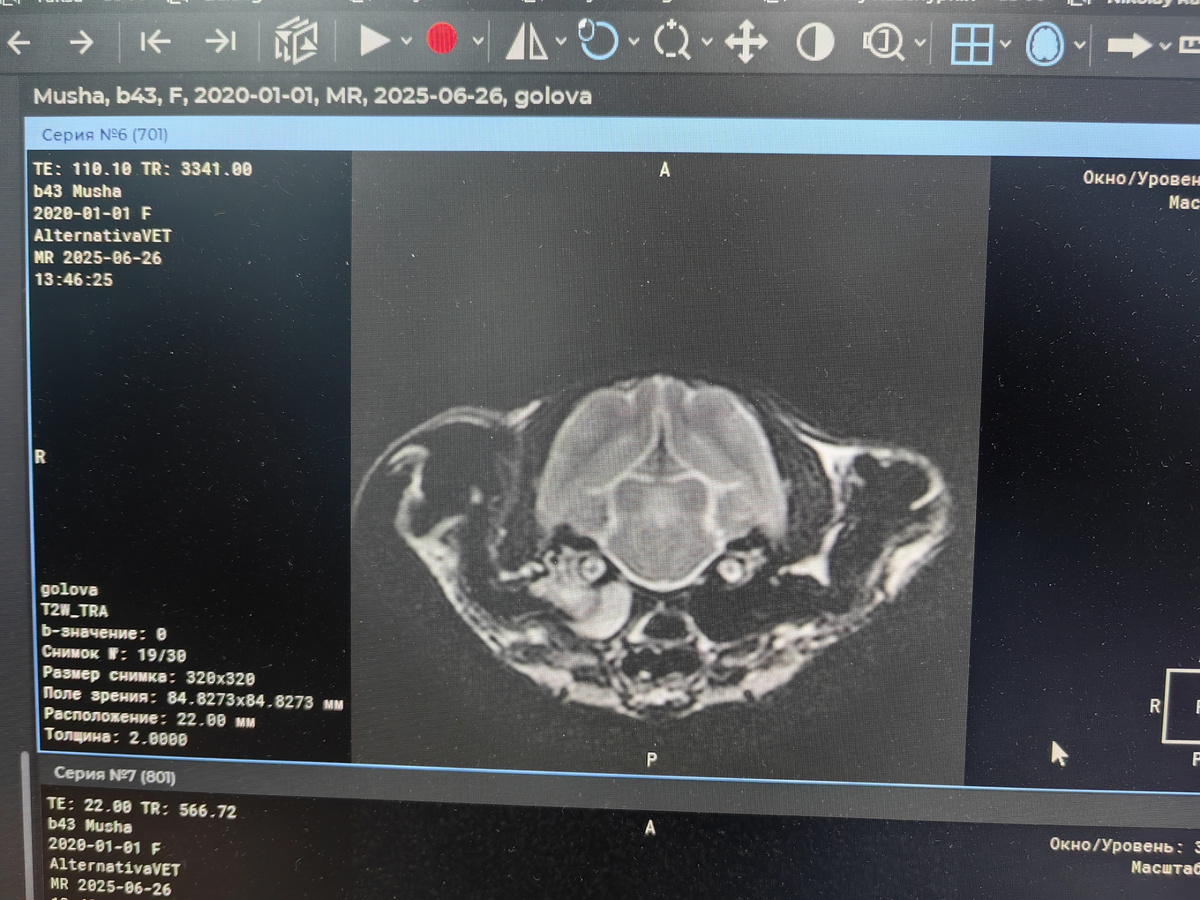

МРТ Мыши

Сделали МРТ - диагноз отит среднего уха. Полностью внутри всё заполнено жидкостью. Нужно делать тяжелую сложную операцию буллутомию. Без нее Мыша погибнет. Точную сумму не знаю. Обычно это от 15000р

За МРТ и анализы крови отдали 10600р